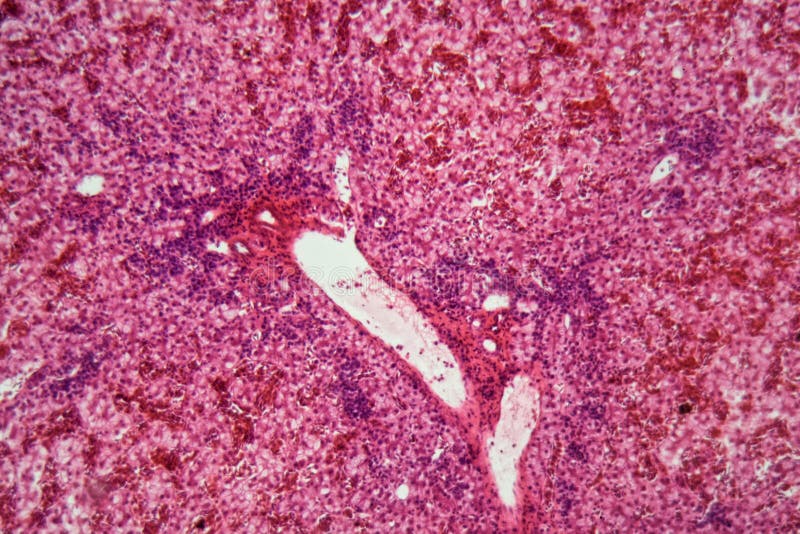

Postmortem liver biopsy showing (A) focal areas of liver cell necrosis Liver Cells Dying We then review the clinical relevance of cell death, focusing on biomarkers; Growing evidence from our increasing understanding of the biochemical and molecular mechanisms involved in cell demise has provided an expanding view of various. Cell death is a fundamental driver of liver disease progression to liver fibrosis, cirrhosis and hepatocellular carcinoma. Hepatocellular death is present in almost all types. Liver Cells Dying.